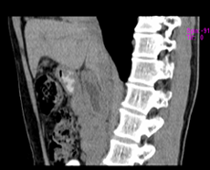

患者,男,57,常年不吃午饭,近一个月来腹部隐痛,无明显黄疸,明天进行增强扫描,图象另上传,麻烦各位帮忙一起看看讨论讨论

肝外胆管扩张,胰头增大,肠系膜上静脉似有包埋征象。

考虑:胰头占位性病变,建议增强进一步检查。

肝外胆管稍扩张,胰腺钩突略增大,但外形尚可,境界清楚。(常年不吃午饭)提示胰腺炎可能大,肿瘤第二步考虑。

支持考胰头占位性病变,感觉十二指肠壁不规则增厚,不排除十二指肠降部占位可炎症

胰头增大,胆总管增宽,考虑胰头癌可能性大,明天看增强片有助诊断.